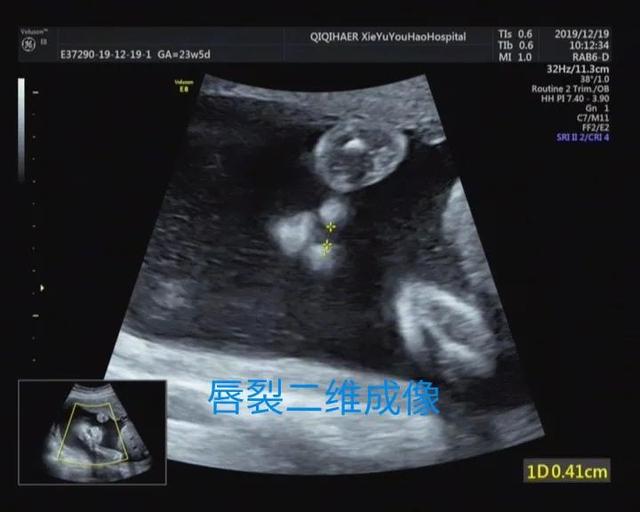

妈妈们更关心的是2D超声和3D超声的区别,简单的科普讲解,超声医生通过多切面和动态2D超声诊断畸形,3D成像只是在必要的时候起到辅助作用。胎儿表面结构的三维图像客观真实。一旦出现胎儿体表畸形,如唇裂、脑膨出、脊柱裂、脐膨出、腹裂、四肢、手脚畸形等,三维影像可以让孕妇及其家属一目了然,便于产科医生或儿科医生根据实际情况提供建议和意见,方便选择下一步的治疗方案。这里有几个小案例,读者可以自己体验一下。

案例2